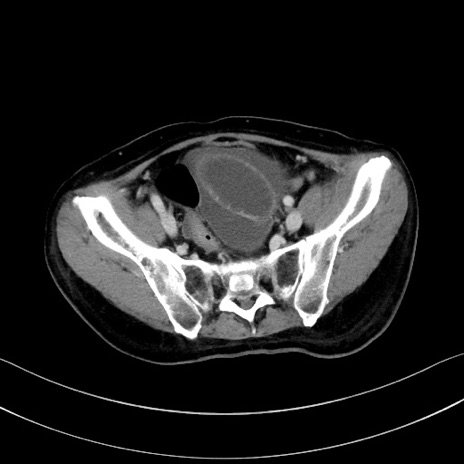

症例28(横断像)

【症例】60歳代男性

【主訴】嘔吐

【現病歴】胃癌にて胃全摘後。食思不振が悪化し、夜中に嘔吐することがある。

【既往歴】胃癌、胃全摘、脾摘、胆摘後

【データ】WBC 5900、CRP 10.56